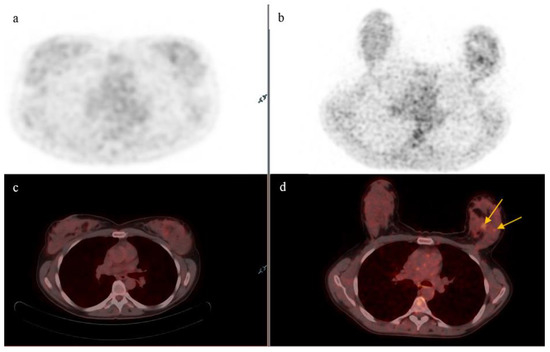

3.2. Lymph Nodes